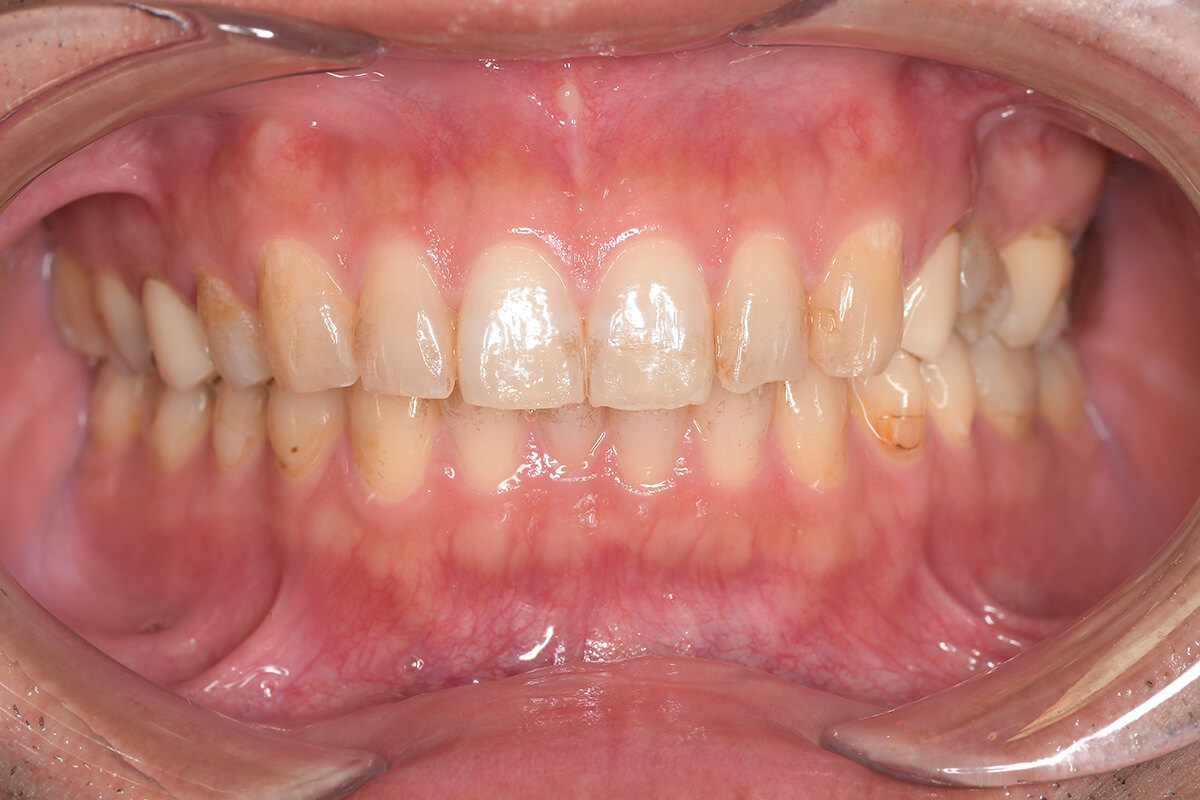

CASE 3

Before

After

基本情報

| 年齢・性別 | 30代・女性 |

| 主訴 | 定期検診 |

| 治療内容 | PMTC |

| 治療期間 | 60分 |

| 治療費 | 5,750円 |

| リスク・副作用 | しみる可能性があります。 |

| 治療方針 | PMTCでステインの除去。 |

| 担当者所見 | ステインが付きやすいため、3カ月毎の定期検診で除去する。 |